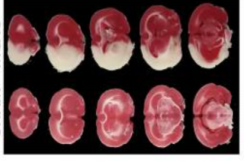

③TTC染色(金标准):TTC染色是TTC和活细胞线粒体内的琥珀酸脱氢酶反应,生成红色的甲臜,用来表示细胞的活力。实验多配制2%染液浓度,染色过程要在37℃条件下避光进行,TTC染色可直观评估MCAO梗塞程度(如图1所示),白色代表脑梗塞区域。

MCAO组和正常组

图1:TTC染色的脑切片[2]